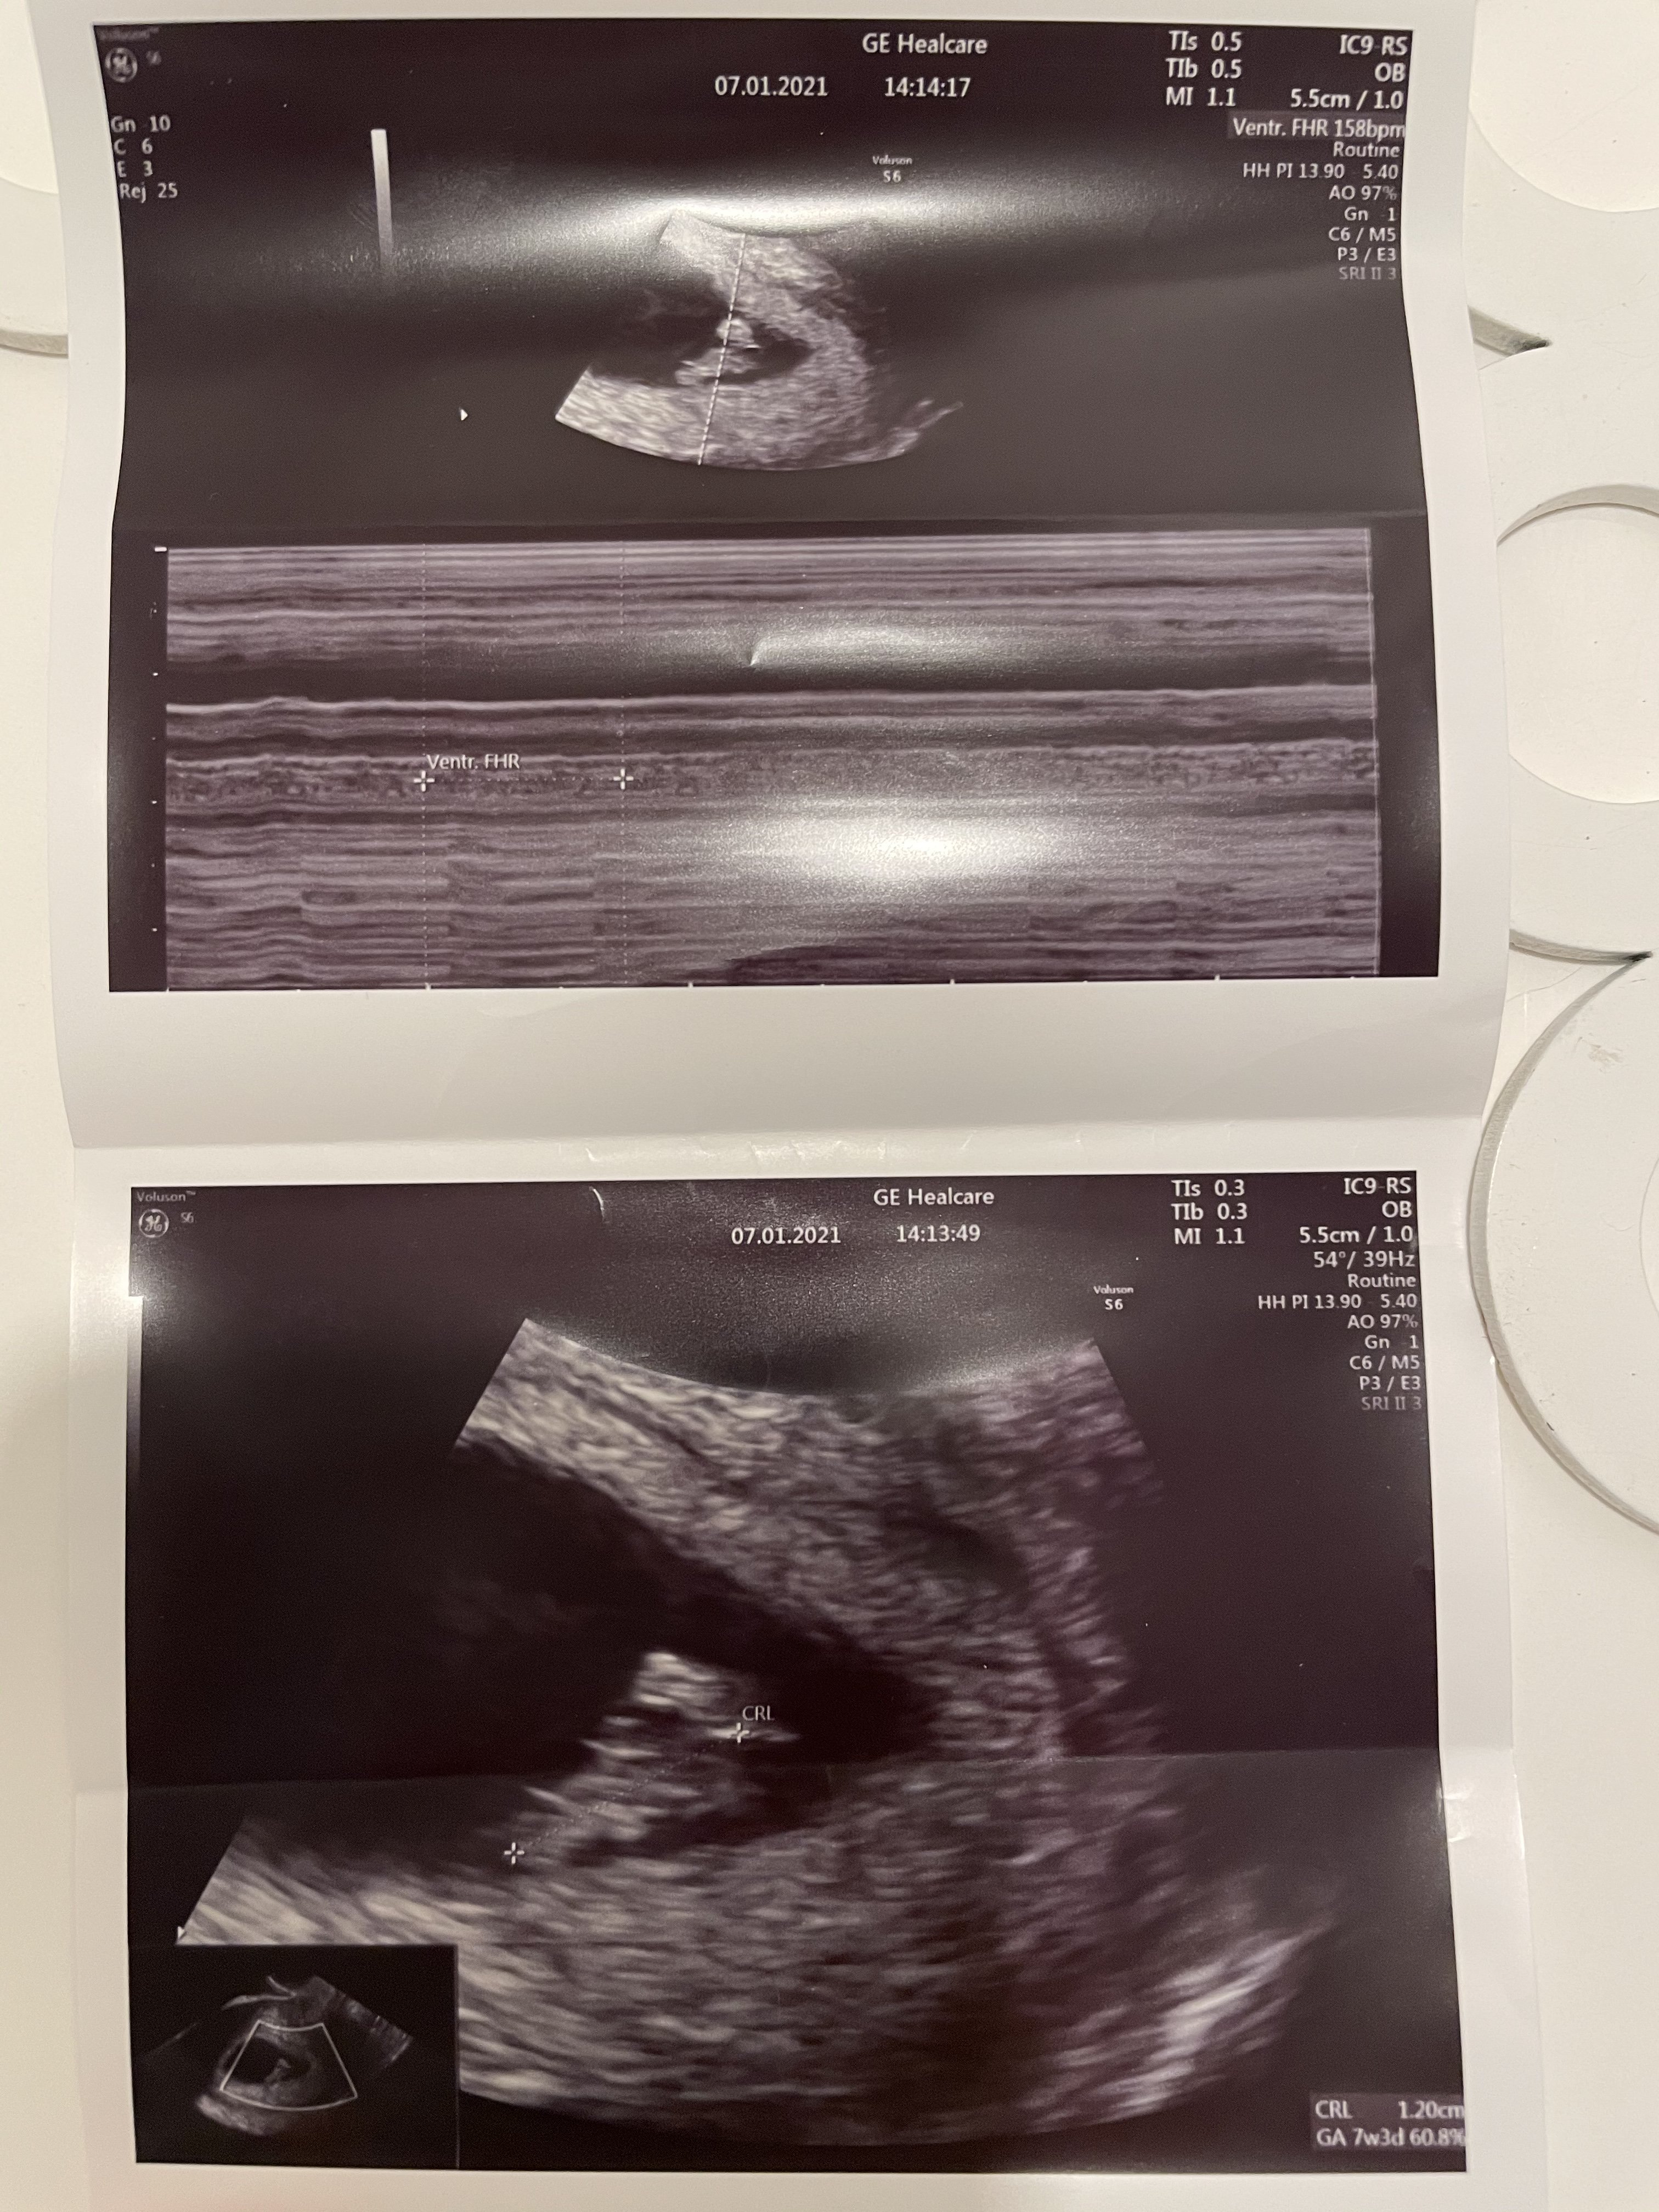

Hej Dziewczyny👋🏻😁 Pędzę do Was z info prosto z wizyty. Stres miałam na poczekalni niesamowity, serce mi waliło jak oszalałe czy wszystko jest ok i okazuje się, ze jest! 😁 Z USG 7+3, widać było zarodek i bijące serduszko💗 tętno 158, ciąża na tę chwilę rozwija się prawidłowo, ale pani doktor zaleciła nie informować nikogo do 3 miesiąca. Pani doktor sama z siebie zapytała czy poprosić do gabinetu partnera, żeby zobaczył badanie na żywo, bardzo miło z jej strony🙂 Kolejną wizytę mam 21.01.

Hej Dziewczyny[emoji1309][emoji16] Pędzę do Was z info prosto z wizyty. Stres miałam na poczekalni niesamowity, serce mi waliło jak oszalałe czy wszystko jest ok i okazuje się, ze jest! [emoji16] Z USG 7+3, widać było zarodek i bijące serduszko[emoji175] tętno 158, ciąża na tę chwilę rozwija się prawidłowo, ale pani doktor zaleciła nie informować nikogo do 3 miesiąca. Pani doktor sama z siebie zapytała czy poprosić do gabinetu partnera, żeby zobaczył badanie na żywo, bardzo miło z jej strony[emoji846] Kolejną wizytę mam 21.01.